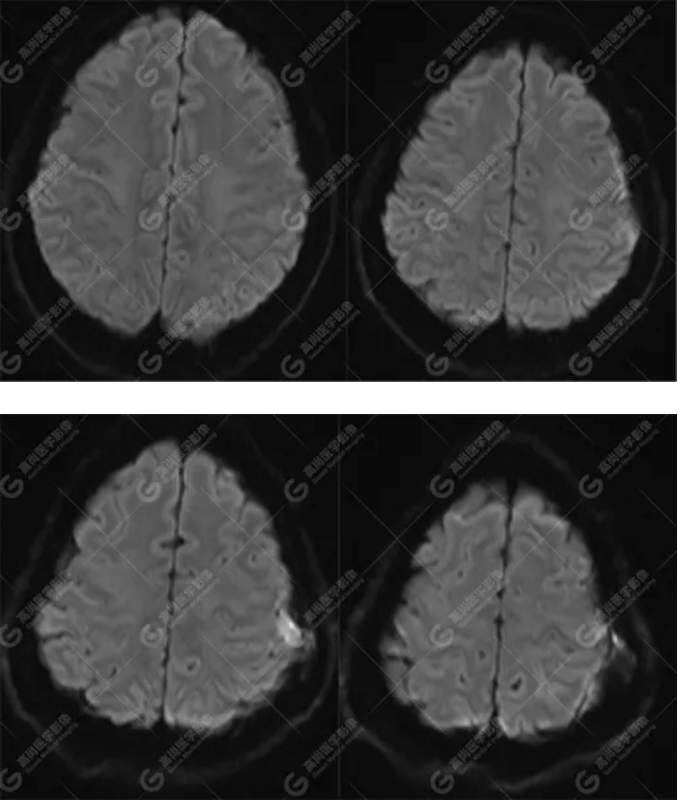

中年男性,反復(fù)出現(xiàn)手腳抽搐、暈倒伴意識(shí)喪失3年余,臨床擬診癲癇發(fā)作,后到高尚醫(yī)學(xué)影像診斷中心行MR檢查。

MR圖像

左側(cè)額頂部顱骨骨質(zhì)破壞并相鄰硬腦膜增厚強(qiáng)化,考慮Rosai Dorfman病(RDD)可能,需與朗格漢斯細(xì)胞組織細(xì)胞增生癥鑒別。

繼發(fā)性中樞神經(jīng)系統(tǒng)淋巴瘤常累及腦膜,呈 T1WI 等或稍低信號(hào)、T2WI 等信號(hào)且信號(hào)均勻,DWI 多呈高信號(hào),鈣化、出血少見,增強(qiáng)掃描后腫瘤整體均勻強(qiáng)化,有文獻(xiàn)報(bào)道強(qiáng)化后病灶內(nèi)部可見細(xì)線樣“放射狀”改變,這種特異的強(qiáng)化方式有助于與 RDD 鑒 別;

總之,顱內(nèi)RDD是一種罕見的硬腦膜良性病變,若 MRI發(fā)現(xiàn)顱內(nèi)基于硬腦膜扁平或匍匐生長(zhǎng)的孤立或者多發(fā)腫塊,CT 檢查未見鈣化,而MR檢查T2WI及 DWI呈低信號(hào),增強(qiáng)明顯均勻強(qiáng)化,應(yīng)考慮到 RDD 的可能。